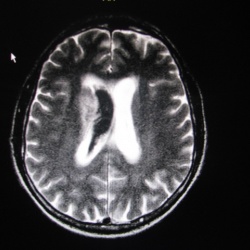

Беспокоили головные боли, несколько лет, легкий экзофтальм слева. От всех "оперативных" действий медиков категорически отказалась. Осталась единственная ЭРГ